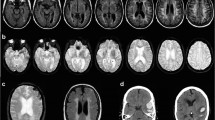

Cerebral amyloid angiopathy (CAA) was found in 57% of 123 autopsy brains removed from patients aged 59–101 years. The incidence of CAA increased with age. CAA was seen most frequently in the occipital cortex. Immunohistochemically, amyloid of CAA was positive for amyloid P component and negative for human AA protein and human prealbumin. The presence and severity of CAA were significantly correlated with the number of senile plaques and neurofibrillary tangles. The incidence of CAA in 17 patients with dementia of Alzheimer type (DAT) was estimated to be 88% and was significantly higher than that in 26 patients with dementia of non-Alzheimer type. CAA had a pathogenetic relationship with both brain ageing and DAT. Lobar cerebral haemorrhage was found in 3 patients with CAA of marked or moderate degree. Lobar cerebral haemorrhage in the aged and in patients with DAT suggest the presence of CAA.